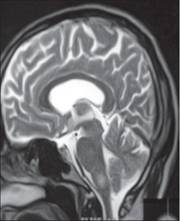

Tuy nhiên, một ngày sau khi trở về nhà bệnh nhân trở nên nói rời rạc, không rõ ràng và tâm lý bất bình thường và hành vi không hợp tác. Anh ta phải nhập viện trở lại vào ngày thứ 22. Khi thăm khám, thân nhiệt là 37.8°C nhưng không phát hiện nhiễm trùng trên lâm sàng, không có dấu màng não và không có dấu thần kinh gì bất thường khác hơn là cơn lú lẫn cấp và thang điểm Glasgow 12/15. Đường máu, pH máu, khí máu động mạch bình thường. CT và chụp gadolinium-enhanced T1- & T2-weighted MRI scans não cũng cho hình ảnh bình thường. Phân tích mẫu dịch não tủy chọc ra cho thấy dịch không màu, trong suốt, có 4 bạch cầu lymphocytes/mm3, đường trong dịch não tủy bình thường và tăng protein lên 0.89 g/L (BT: 0.2–0.4 g/L). Bệnh nhân được điều trị ngay bằng thuốc cefotaxime và aciclovir tiêm tĩnh mạch.

Tuy nhiên, vào ngày thứ 13, bệnh nhân sốt tái phát và có các triệu chứng thần kinh tăng gấp 3 lần: co giật cơ cảnh tay và chân, mà điều này rất nhạy với thính giác và cảm giác, rung rủ cánh thân mình, rối loạn ngôn ngữ không có liên quan đến các đặc điểm rối loạn chức năng không gian thời gian khác. Chụp CT và chụp MRI có gadolinium-enhanced T1- and T2-weighted MRI scans não bộ cho hình ảnh bình thường. Khi phân tích dịch não tủy, áp lực bình thường (12 cm), tăng nồng độ protein đáng kể (2.39 g/L), 59 lymphocytes/mm3 và nồng độ glucose bình thường. Cấy dịch não tủy vô trùng với vi khuẩn và virus, kháng nguyên cryptococcus âm tính và PCR đối với herpes cũng như M. tuberculosis đều âm tính.

Matias G, Canas N, Antunes I, Vale J. đang làm việc tại khoa thần kinh, bệnh viện Egas Moniz, Lisboa Med Port vào năm 2008 công bố về hội chứng này có đề cập: các triệu chứng thần kinh trên sốt rét thường có liên quan nhiễm trùng nặng do Plasmodium falciparum. Ít gặp hơn, suy giảm ý thức, động kinh và khuyết tật về thị giác cũng như thính giác là có liên quan đến hạ đường huyết (do sốt rét hoặc do thuốc quinine) hoặc độc tính của thuốc. Trong những năm trước đây, nó được nhận ra là một biến chứng thần kinh hiếm sau khi điều trị sốt rét do Plasmodium falciparum - Hội chứng PMNS. PMNS xảy ra từ vài ngày đến vài tuần sau khi đã làm sạch ký sinh trùng, biểu hiện bởi một hội chứng hay bệnh lý não với độ trầm trọng khác nhau. Cơ chế bệnh sinh liên quan đến PMNS vẫn chưa được hiểu thấu đáo, có thể nghĩ đến do nguyên do miễn dịch. Ca bệnh báo cáo ở đây là một đàn ông 61 tuổi có biểu hiện bệnh lý não nghiêm trọng (cơn mê sảng, thất điều tiểu não và ophthalmoparesis), 2 ngày sau khi hồi phục hoàn toàn sốt rét Plasmodium falciparum. Xét nghiệm máu ngoại vi lặp lại âm tính. Chụp MRI trong pha cấp chỉ ra có những bất thường chất trắng đa ổ lan tỏa. Bệnh nhân được điều trị bằng thuốc methylprednisolone liều cao đã giải quyết các khiếm khuyết thần kinh hoàn toàn. Sau 9 tháng chụp lại MRI chỉ thấy các tổn thương tồn lưu rất bé.

Nhóm tác giả A H Mohsen, M W Mckendrick, M L Schmid, S T Green đang công tác tại khoa truyền nhiễm và y học nhiệt đới, Bệnh viện hoàng gia Hallamshire, Sheffield, Anh và khoa Thần kinh lâm sàng, khoa chẩn đoán hình ảnh về thần kinh báo cáo bệnh nhân nữ 30 tuổi với rối loạn thần kinh 8 tuần sau khi hồi phục hoàn toàn từ sốt rét Plasmodium falciparum. Chụp MRI trong lúc bị bệnh cho thấy các hình ảnh bất thường các chất trắng đa ổ (multifocal white matter abnormalities). Cô ta hồi phục hoàn toàn mà không cần bất cứ điều trị đặc hiệu nào. Chụp MRI lặp lại 6 tháng sau đó cho thấy tất cả thương tổn đã được giải quyết. Mặc dù thuật ngữ của hội chứng PMNS đã được dùng để mô tả những ca như thế, song hình ảnh lâm sàng và các chỉ số cận lâm sàng không thể phân biệt được với các bệnh lý viêm não tủy lan tỏa cấp tính (acute disseminated encephalomyelitis).